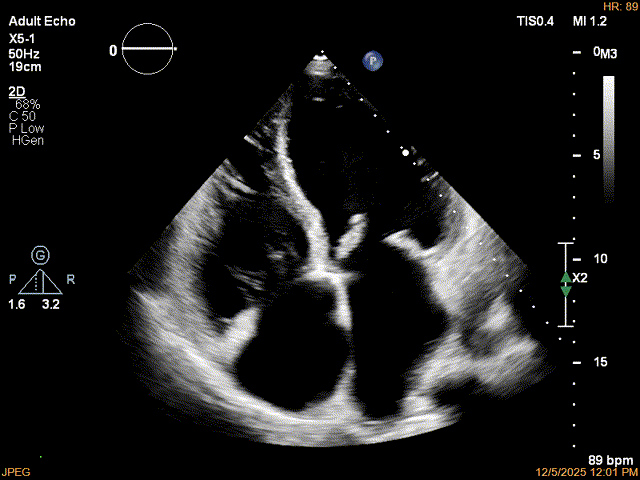

术后影像

最终结果3D-Zoom-color显示组织桥稳定,原脱垂区域前后叶对合部分的脱垂已消除,反流降至1+以下

夹子释放Bi-com切面显示残余反流情况

肺静脉收缩期逆流消失,频谱形态基本恢复正常

术后2D TTE:

术后TTE可见二尖瓣微量-轻度反流,三尖瓣反流明显改善降至中度